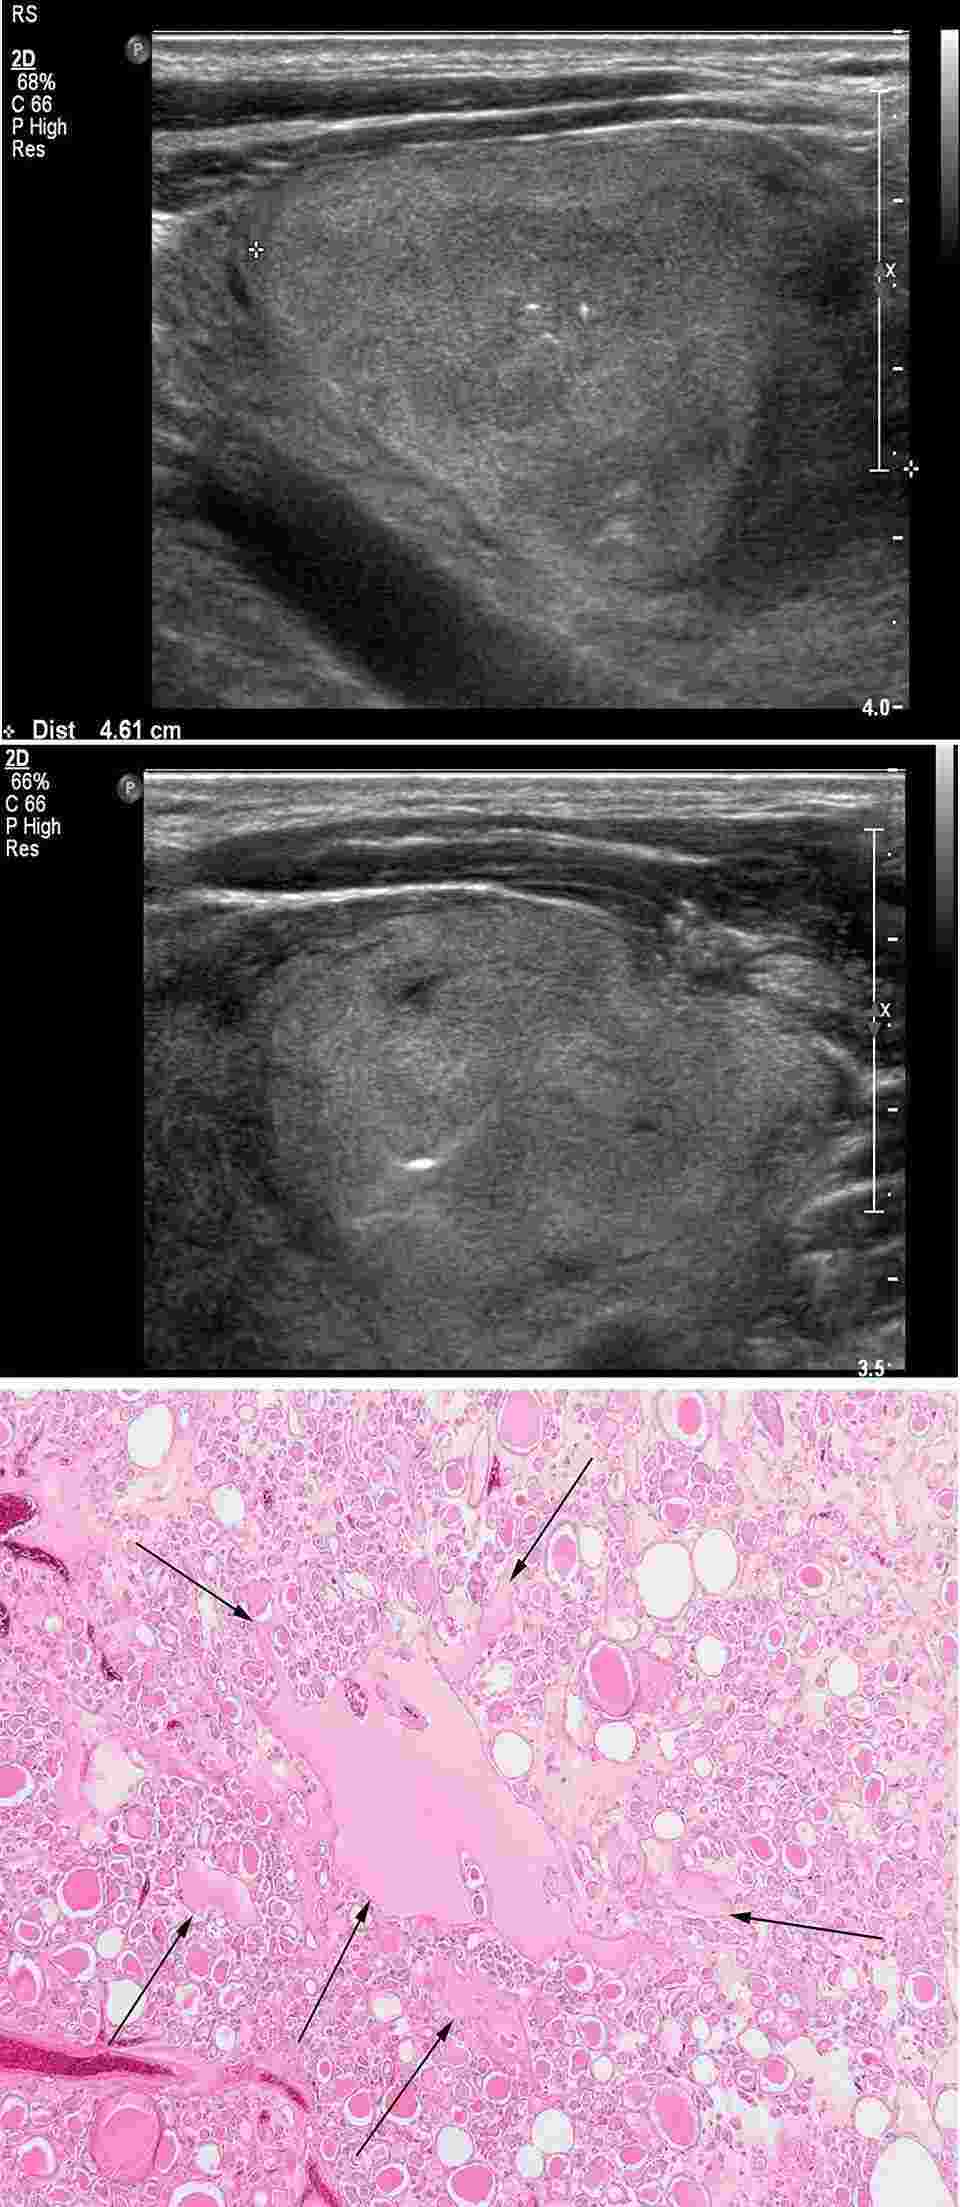

Images from a representative follicular adenoma case.Fig.1 Images of a representative case of follicular adenoma.1

Follicular adenoma is a benign encapsulated tumor of the thyroid gland. It is a firm or rubbery, homogeneous, round, or oval tumor that is surrounded by a thin fibrous capsule. Most patients with a follicular adenoma are clinically and biochemically euthyroid, where the thyroid adenoma is silent. However, about 1% of follicular adenomas are functional tumors, producing excessive thyroid hormone and resulting in symptomatic hyperthyroidism. In this case, these functioning follicular adenomas avidly concentrate radioiodine, leading to the suppressive iodine uptake in the rest of the thyroid gland.

An ultrasound examination of the thyroid gland is recommended in all patients with a thyroid nodule to help characterize the nodule as well as to examine the rest of the thyroid gland for other nodules. Although this technique alone cannot distinguish a follicular adenoma from a carcinoma, sonographic features such as hypoechogenicity, punctuate microcalcifications, indistinct or irregular margins are signs of a higher risk of malignancy. Moreover, all patients with nodular thyroid disease should have a serum TSH level measured to evaluate the functional status of the thyroid gland. Usually, a low serum TSH level suggests a suspicious “toxic adenoma”.

1. Ahn, Hye Shin, Hee Sung Kim, and Min Ji Hong. "Ultrasonographic and cytologic assessments of follicular neoplasms of the thyroid: Predictive features differentiating follicular carcinoma from follicular adenoma." Plos one 17.7 (2022): e0271437. Distributed under Open Access license CC BY 4.0, without modification.